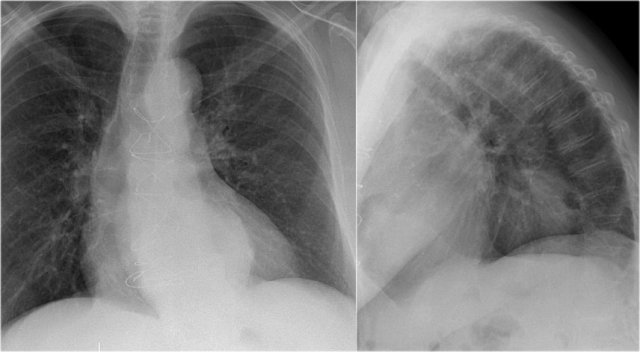

Right ventricle enlargement

First study the PA and lateral chest film and then continue reading.

On these chest films the heart is extremely dilated.

Notice that it is especially the right ventricle that is dilated. This is well seen on the lateral film (yellow arrow).

There is a small aortic knob (blue arrow), while the pulmonary trunk and the right lower pulmonary artery are dilated.

All these findings are probably the result of a left-to-right shunt with subsequent development of pulmonary hypertension.